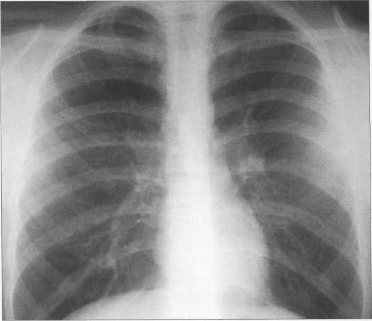

У новорожденных сердце имеет относительно большую величину, СЛК у них может достигать 58% (рис. 9.22). У более старших детей и у взрослых СЛК составляет 44—48%, для большого числа подростков характерны небольшие размеры сердца (СЛКменее 40%) (рис. 9.23),улюдей пожилого возраста поперечные размеры сердца увеличиваются, СЛК у них, как правило, более 50%.

Рис. 9.23. Рентгенограмма грудной клетки подростка. Передняя проекция.

Левый контур образуют 4 дуги: дуга аорты, легочный ствол, ушко левого предсердия, левый желудочек. В детском возрасте (приблизительно до 7 лет) протяженность дуги легочного ствола преобладает над протяженностью дуги аорты, в дальнейшем протяженность дуг становится одинаковой. У подростков и людей астенического сложения дуга легочного ствола выпрямленная или выпуклая (см. рис. 9.23), у взрослых она, как правило, вогнутая. Левая граница сердца на уровне левого желудочка находится на уровне среднеключичной линии или на 1 см кнутри от нее.